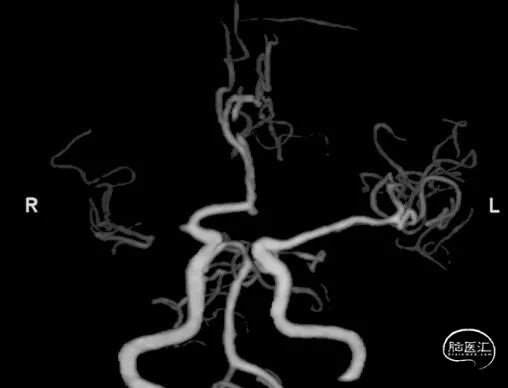

术前影像信息

右侧大脑中动脉闭塞。

④ CTA上可以看到M1水平段闭塞,而M2段以远可以看到稀疏的血管显影,为非栓塞性的常见位置。

术前正侧位造影。